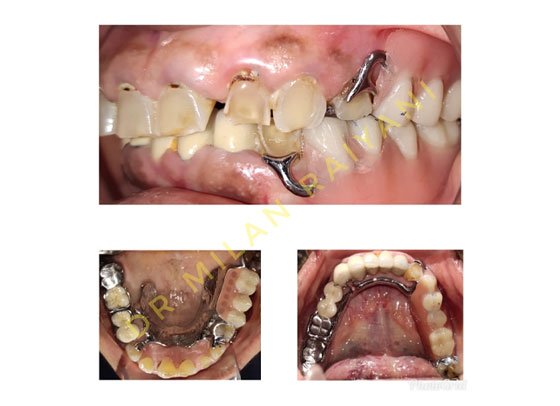

GALLERY